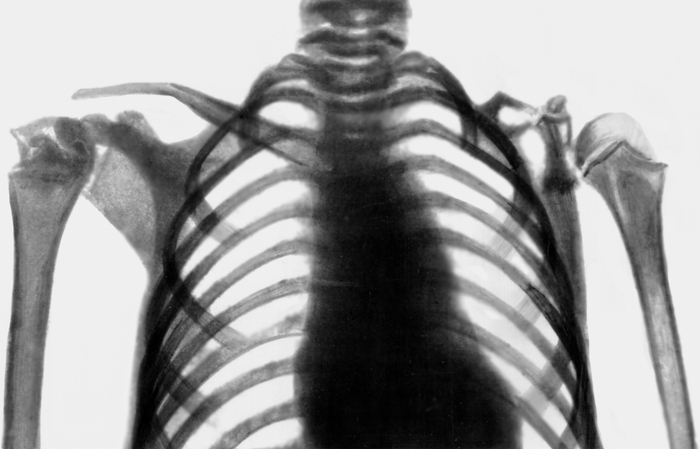

Медицина и диагностика: Аномалии ребер на рентгене